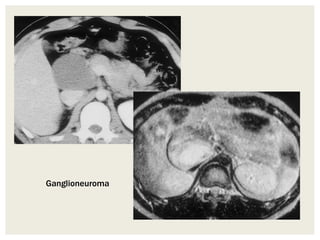

Ganglioneuromas

CT

• Typically seen as well-circumscribed, solid,

encapsulated masses that are iso to hypoattenuating to

muscle.

• Calcifications is seen in ~20% of the cases, and are typically

discrete and speckled

MRI

• Well circumscribed encapsulated masses with variable signal

intensities and enhancement characteristics

• ADC: ADC values tend to be higher to that of a neuroblastoma

Ganglioneuroma